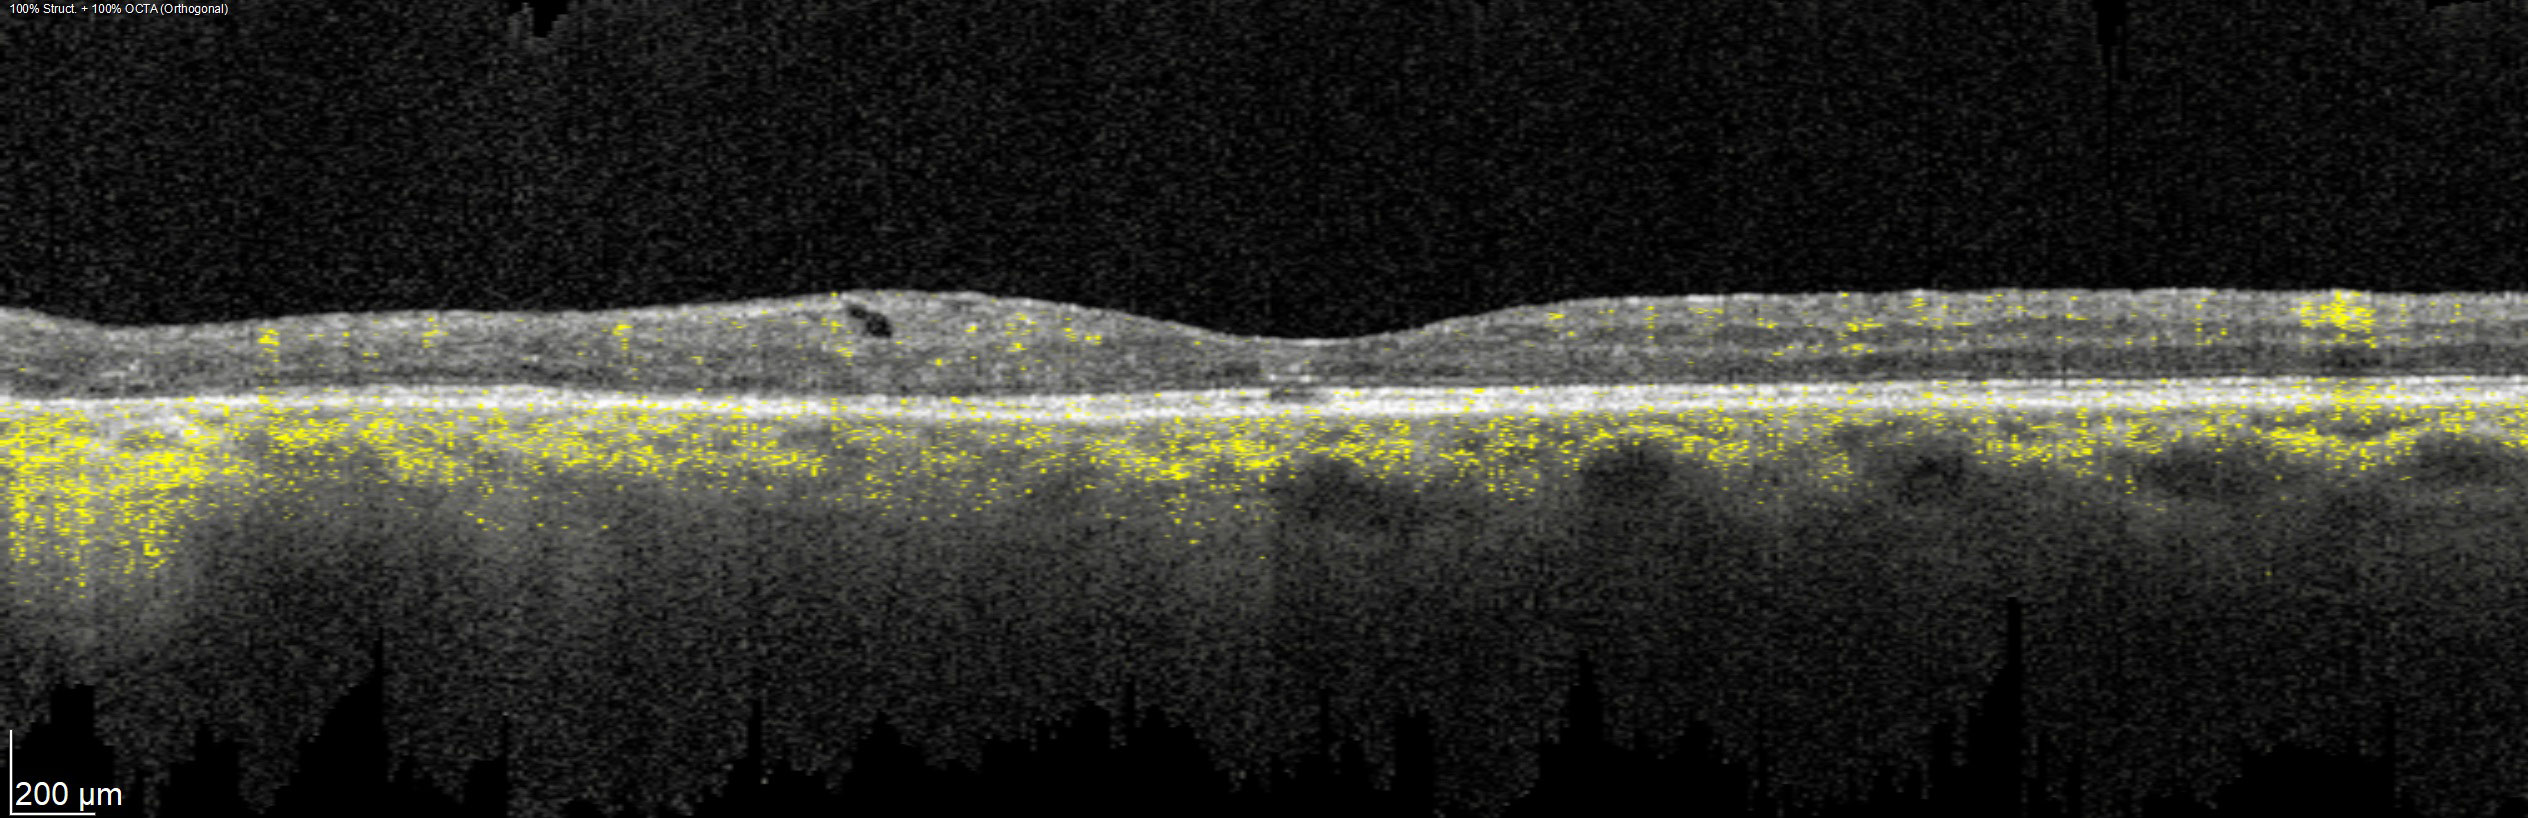

Offering the ideal speed-quality ratio for OCTA, 125 kHz allows you to increase your throughput without any clinically relevant loss in image quality in comparison to the current 85 kHz scan speed. The fast acquisition of images allows for visualization of flow, even in miniscule vessels, while minimizing artefacts, resulting in sharp and detailed images of the capillary network. Additionally, you can decrease chair time when you speed up acquisition with the Glaucoma Module Premium Edition in your glaucoma workflow, if applicable.

SPECTRALIS with SHIFT technology and 125 kHz scan speed empowers you to offer customized diagnostic OCTA imaging of both the retina and the optic nerve head to meet the needs of each individual patient – or adjust to 85 kHz if your patient’s condition requires longer light exposure.

125 kHz – A fast scan speed for improved workflow and high OCTA image quality.